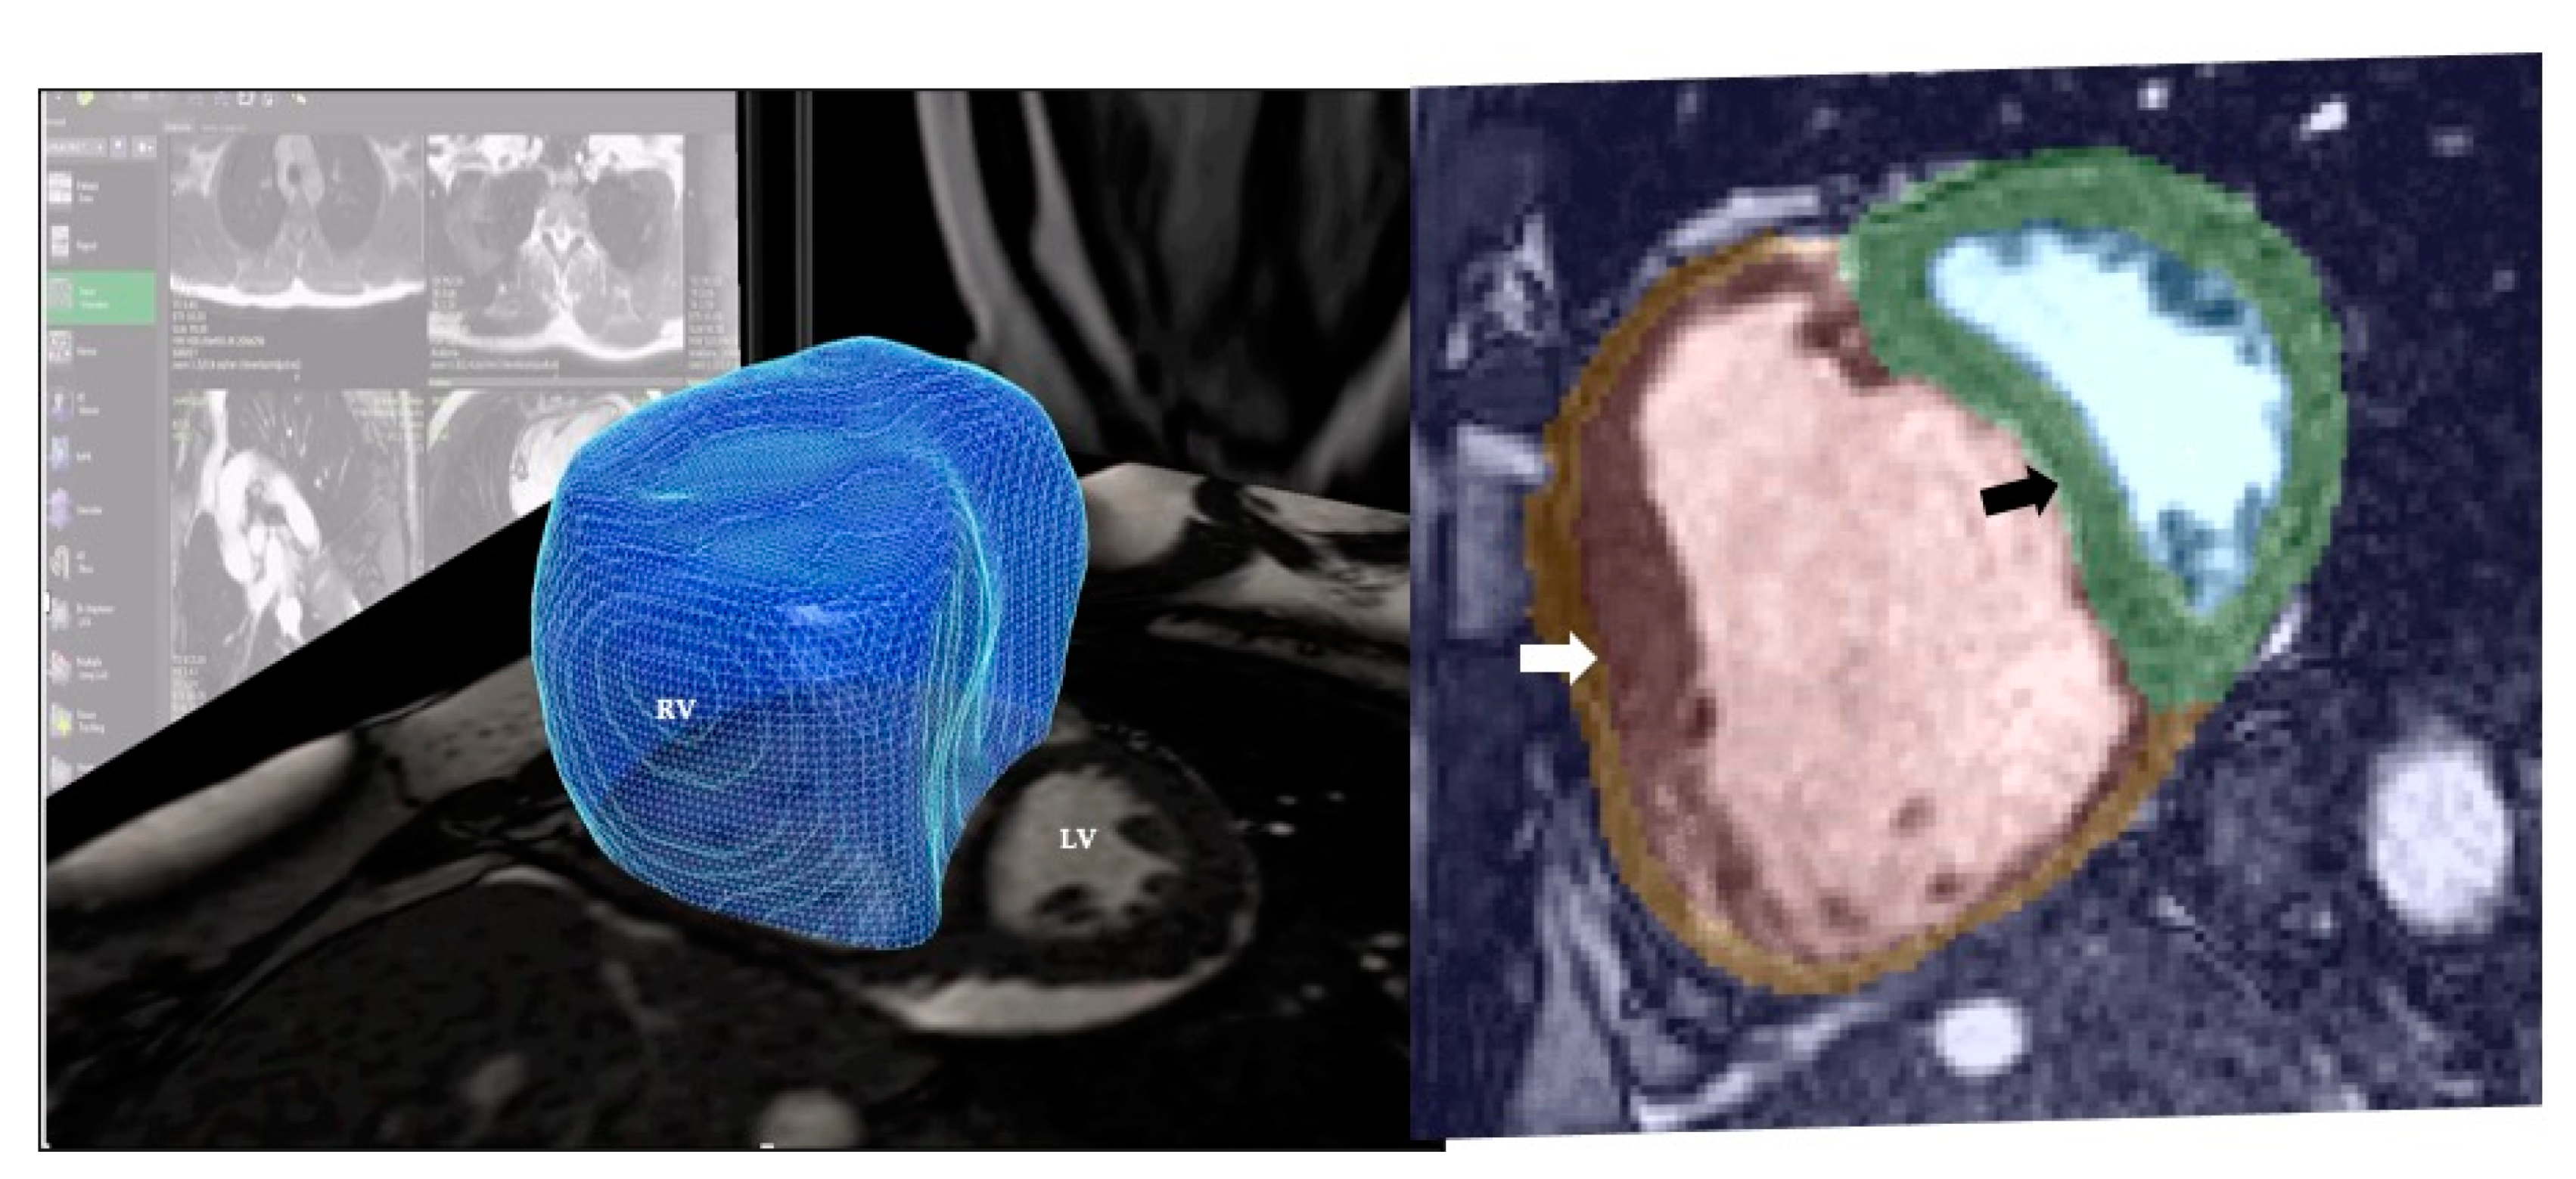

5.4. Cardiovascular Magnetic Resonance (CMR)

- Avendi, M.R.; Kheradvar, A.; Jafarkhani, H. Automatic Segmentation of the Right Ventricle from Cardiac MRI Using a Learning-Based Approach: Automatic Segmentation Using a Learning-Based Approach. Magn. Reson. Med. 2017, 78, 2439–2448. [Google Scholar] [CrossRef]

- Mauger, C.; Gilbert, K.; Lee, A.M.; Sanghvi, M.M.; Aung, N.; Fung, K.; Carapella, V.; Piechnik, S.K.; Neubauer, S.; Petersen, S.E.; et al. Right Ventricular Shape and Function: Cardiovascular Magnetic Resonance Reference Morphology and Biventricular Risk Factor Morphometrics in UK Biobank. J. Cardiovasc. Magn. Reson. 2019, 21, 41. [Google Scholar] [CrossRef]

- Swift, A.J.; Lu, H.; Uthoff, J.; Garg, P.; Cogliano, M.; Taylor, J.; Metherall, P.; Zhou, S.; Johns, C.S.; Alabed, S.; et al. A Machine Learning Cardiac Magnetic Resonance Approach to Extract Disease Features and Automate Pulmonary Arterial Hypertension Diagnosis. Eur. Heart J.—Cardiovasc. Imaging 2020, jeaa001. [Google Scholar] [CrossRef]

- Dawes, T.J.W.; de Marvao, A.; Shi, W.; Fletcher, T.; Watson, G.M.J.; Wharton, J.; Rhodes, C.J.; Howard, L.S.G.E.; Gibbs, J.S.R.; Rueckert, D.; et al. Machine Learning of Three-Dimensional Right Ventricular Motion Enables Outcome Prediction in Pulmonary Hypertension: A Cardiac MR Imaging Study. Radiology 2017, 283, 381–390. [Google Scholar] [CrossRef]